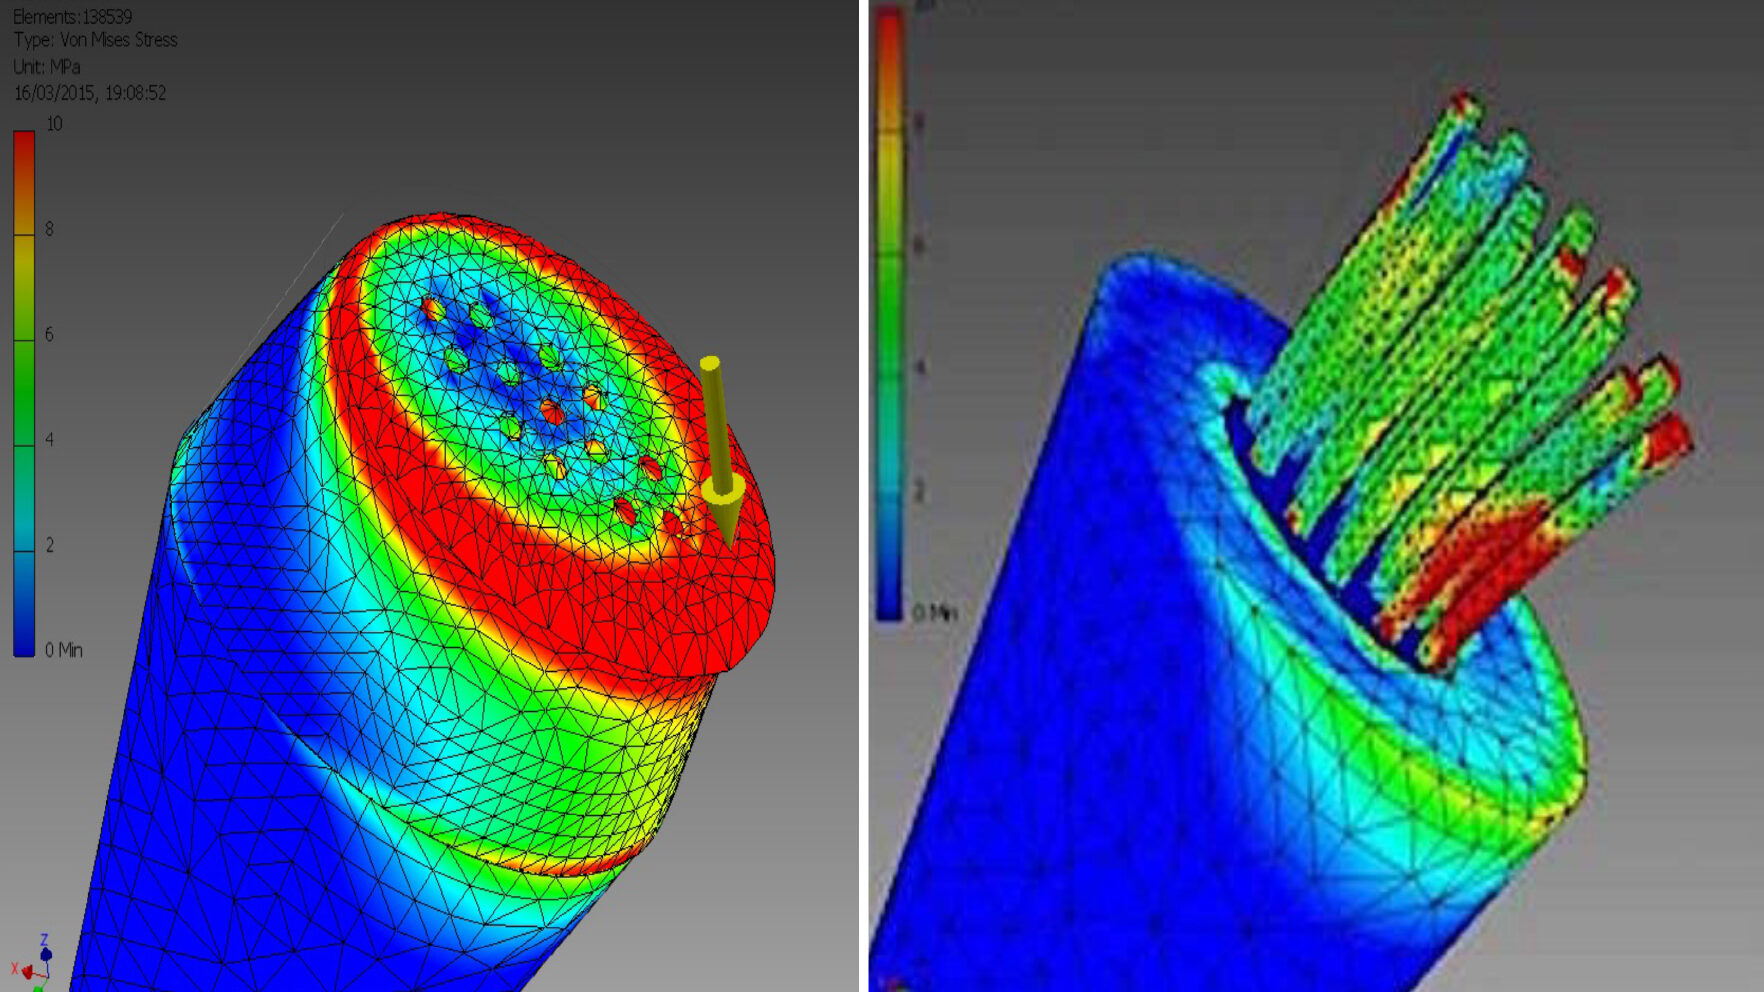

Edentulism in the posterior maxillary region presents a challenging scenario for dental implant rehabilitation due to vertical ridge dimension bone loss and the close proximity to the floor of the maxillary sinus. In addition, alveolar ridge width loss and thinning of mucosa is a common clinical scenario in areas of long term tooth loss. To … Read more